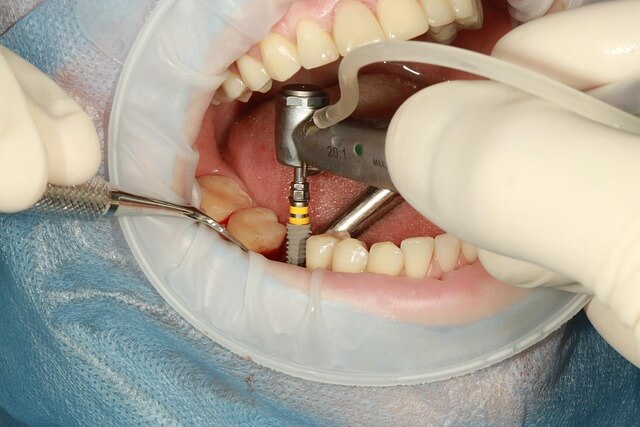

* 사랑니 발치는 국소 마취 하에 안전하게 진행되고 있으며, 최신 치료법 덕분에 통증과 회복 기간이 크게 줄어들었죠.

- * 1-2. 마취 대기 및 준비: 국소마취 후 마취가 충분히 될 때까지 15~20분 정도 기다립니다.

- * 1-3. 실제 발치 시술: 보통 5~15분 사이지만, 매복된 사랑니는 30분 이상 걸릴 수도 있습니다.

- * 1-4. 지혈 및 봉합: 발치 후 출혈을 막고 봉합하는 데 10~15분 정도 추가됩니다.